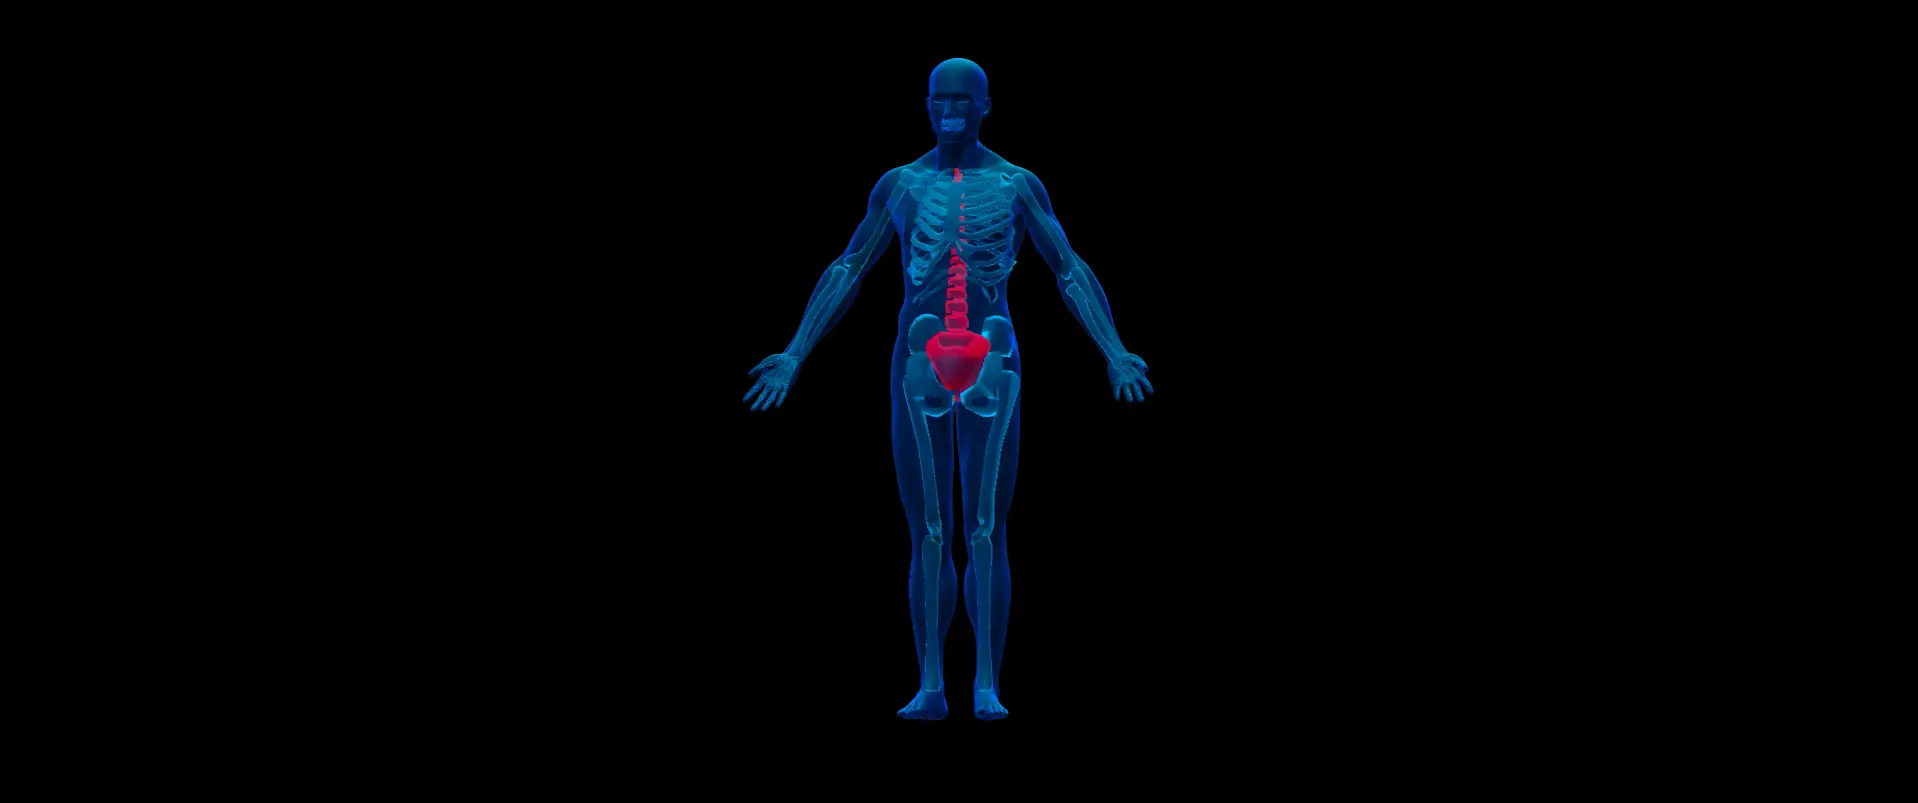

3D Spline Modeling

I design 3D models and interactive visualizations in Spline to bring depth, realism, and engagement to your site, making your content more dynamic and memorable.